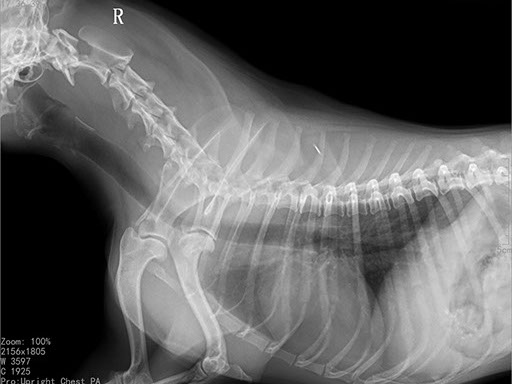

Коллиматорный прицел формирует пучок рентгеновского излучения на участок исследования. Проходя через ткани тела, излучение попадает на плоскопанельный цифровой детектор, который, в свою очередь, передает сигналы на компьютер.

В считанные секунды полученные данные обрабатываются компьютером посредством установленной на него программы визуализации, и сформированное клиническое изображение выводится на монитор лаборанта.

Клинические изображения (снимки) можно напечатать на принтере, сохранить в архиве или отправить по сети коллегам для оперативного консилиума.